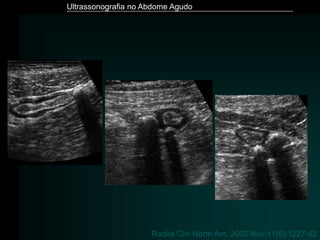

Diverticulite

– Doença diverticular dos cólons

» 1/3 população > 50 anos

» 2/3 população > 80 anos

– Diverticulite aguda

» 25% da população com doença diverticular

– Inflamação aguda de um ou mais divertículos cólicos

– 90% cólon sigmóide

• Ultrassonografia - Fase inicial

» Imagem de adição hipoecóica – divertículo

» halo hiperecóico – processo inflamatório da gordura

adjacente

• Ultrassonografia - Fase avançada

» Coleção pericólica, habitualmente com ar

» Espessamento das paredes do cólon

» Perda de definição das camadas do cólon

Radiol Clin North Am. 2003 Nov;41(6):1227-42